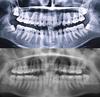

По-моему тут 3 растут неправильно,у меня только одна под таким наклоном и орт сказал,что эта восьмерка никогда не прорежется.

Вот-вот, у меня тож 8 оказалась, как у тебя справа на снимке. Тож в зуб растет. Еще не была на приеме, страшно идти, что скажут

да, три восьмерки неправильно расположены, но мне бы вот тоже хотелось, чтобы они не прорезались никогда))сейчас сижу решаю что же делать-то...удалять из десны уж больно страшно(

мне кажется 3 точно нужно удалить, они не прорежутся и будут оказывать давление на зубной ряд. или ты думаешь что если не прорежутся, то не навредят??? думаю, не рационально оставлять такие зубы-это риск для твоего будущего результата от лечения

А у вас на снимочке видно, что одна восьмерка явно не так расположена, вообще лежит почти, другая восьмерка тоде наклонена, а из-за нее ещё два зуба.

Всё на усмотрение ортодонта. 48 вообще хорошо стоит - его и трогать жалко. Разве что у 38ого уж больно широкая коронка - при таком расположении может не встать в ряд.

Mel, первое фото - осень 2007 года, второе - осень 2012. В 2007 три восьмёрки начали прорезываться, к началу 2011 они уже вышли и встали в дугу, но у меня ОПГ за этот период нет.

это решает врач-хирург. Никак не пользователи. Но на на снимке уже видно, что одна восьмерка растет не правильно.